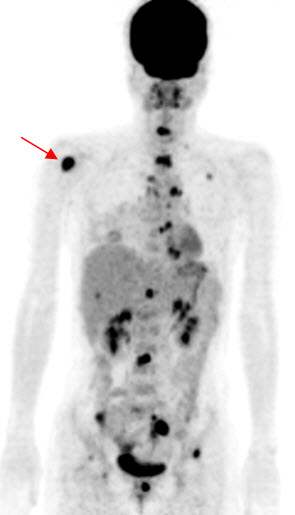

Hình 4 (a, b) cho thấy giá trị của PET/CT trong đánh giá giai đoạn của ung thư vú. Bệnh nhân Nguyễn Th. T. Tr., nữ, 63 tuổi, chẩn đoán là ung thư vú. Kết quả PET/CT toàn thân cho thấy nhiều tổn thương di căn hạch cổ, hạch trung thất, di căn 2 phổi, gan, xương tăng hấp thu FDG.

Hình 4a. Hình PET toàn thân thấy nhiều tổn thương hạch cổ, hạch trung thất (mũi tên vàng), phổi (mũi tên đỏ), gan (mũi tên tím) và xương (mũi tên xanh) tăng hấp thu FDG.